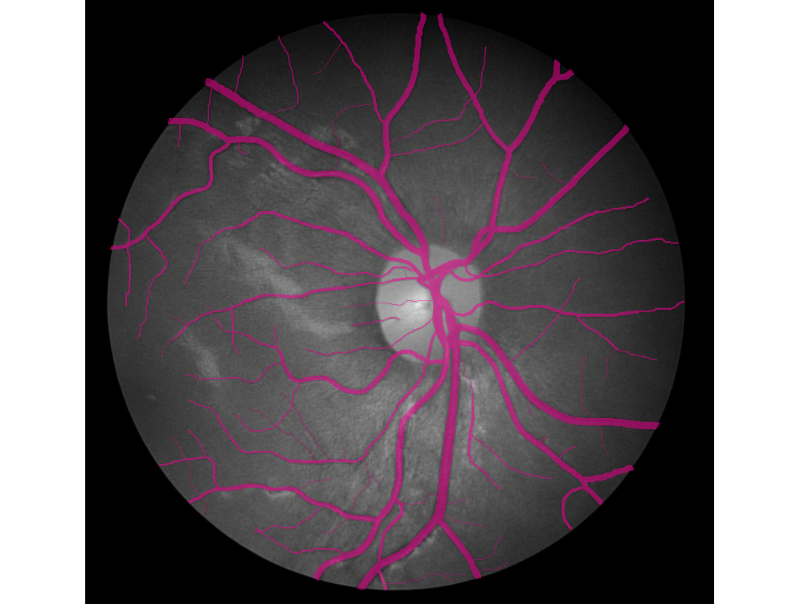

Hello world! In December of 1895, Wilhelm Röntgen the bones of his wife’s hand in the first X-ray photograph. “I have seen my death,” she said. This breakthrough had an incredible influence on 20th-century medical treatment. And latest Deep Learning advances open up new possibilities in this field. revealed Deep Learning has found great success in computer vision and other areas. And now it is actively transforming the world of medicine. AI helps doctors make more accurate diagnoses faster. Today we would like to share our thoughts and investigations into very promising direction: Human in the loop AI for medical image analysis within a single environment — . Supervisely Our platform allows to manage and annotate data, train NNs, apply them for automatic pre-annotation and then deploy them as API. Challenges with medical images IBM researchers that medical images, as the largest and fastest-growing data source in the healthcare industry, account for at least 90 percent of all medical data. estimate Challenge 1: data privacy Medical data is still personal and not easy to access. And due to data privacy concerns most of the public health centers are reluctant to share the data. Challenge 2: size of annotated data Annotation process is hard to outsource and only expert physicians can analyze medical images. This limitation leads to high costs and to the lack of annotated data. Challenge 3: quality of annotation tools Annotation tools, that can be used to extract insights from medical images, are still limited, in most cases publicly unavailable and requiring most analysis to be done manually. Challenge 4 (consequence of 1 and 2): segmentation challenge Datasets for segmentation task are typically extremely small compared to large public datasets of common images (COCO, PascalVoc and so on). Due to the size of datasets it is difficult to train very deep neural network architectures. Objects of interest can vary in size, shape and position. In combination with the “soft” boundaries it produces additional problems. Our goals We are going to overcome Challenge 3 and Challenge 4: give the industry end-to-end solution that makes human experts more efficient and automates routine tasks with powerful AI technologies. Supervisely: user interfaces We realize, that there is still a lot of work ahead: increase the number of convenient annotation tools and add the support of DICOM format, three dimensional images, sequences of images and so on. But these are only technical issues, first steps are already done and promising results are obtained. We are passioned to accelerate medicine and happy to be a part of global research community that drives deep learning revolution to healthcare. There could be no more important application of this new capability [deep learning] than improving patient care — Jensen Huang, NVIDIA CEO and co-founder Case-study: blood vessel segmentation in retina images There are a lot of Deep Learning medical applications in imaging: tumor detection, tracking tumor development, blood flow quantification and visualization, dental radiology and much more. Because we are not doctors, we looked for data we understand more or less. That’s why we decided to make research on blood vessel segmentation. Let’s take a look to one of the most popular public datasets in this field: (STructured Analysis of the Retina). STARE Dataset contains 28 annotated images with resolution 999 × 960. We consider the case that we have only . Other images will be used for final evaluation of quality. All training images are below: 6 annotated images in training dataset Here is the whole training dataset we use. This scenario is pretty close to real world: medical doctor annotates few images, then neural network is trained on this data and applied to other images for pre-segmentation. Then doctor just corrects the NN predictions. Such approach is called Human in the loop AI. It is aimed to significantly accelerate efficiency of human expert. PS. Thanks to Supervisely entire research took 2 hours without haste ☕. Step1: training data augmentation We had only 6 annotated images. To train NN we have to automatically increase the size of dataset. Supervisely has special module to perform augmentations: DTL (Data Transformation Language). It allows to configure entire augmentation process in a simple json-based format and perform it in a few clicks. How DTL query interface looks like In this use case we did horizontal/vertical flips and relatively big random crops. We got 264 training examples from only 6 annotated images. Here is the visualization of computational graph that we applied to our data: Resulted crops after augmentation Step2: train neural network There are few state of the art Neural Networks for semantic segmentation in Supervisely. One of them — our custom UNet-like architecture. It was chosen because: we have small training dataset, it is accurate and fast to train. Also we use combination of Binary Cross Entropy and Dice losses because of class imbalance problem. Vessels pixels covers only few percents of image area in contrast to background pixels. We trained NN 50 epochs. It is interesting to visualize Neural Network predictions during training. We take unseen image and apply NN after each epoch. Here you can see how our NN becomes smarter over time. Supervisely supports multi GPU training. Each epoch takes around 20 seconds on four GPU. Total training time — around 17 minutes. Step3: automatic pre-segmentation We applied NN to new images. Let’s compare predictions with ground truth. : NN predictions, : ground truth Left Right As you can see from this comparison every relatively bold vessels are segmented. There is no noise. It means that the human only have to draw few hairlines with “polyline” tool. Also, as we understand real data has much bigger resolution that public data we use in this experiment. We think that this fact is crucial for the quality of hairlines segmentation. Resolution of publicly available images is not enough. Look at this example: do you see the vessels that are annotated by doctors? Left: meme, Middle: original image, Right: doctor’s annotation Step4: manual correction As you can see from images above the quality of automatic pre-annotation is pretty good. It is much more easier and faster to correct NN predictions than annotate from scratch manually. We were not lazy and made time measurements: how much time we need for manual annotation from scratch vs correction of NN predictions. Manual annotation from scratch: . Correction of NN predictions: . 36 minutes / image 4 minutes / image Conclusion is obvious. Final thoughts Deep Learning has a huge potential in medical image analysis. AI is changing the way doctors diagnose illnesses. Main important difference between doctor and deep learning algorithm is that doctor has to sleep. Neural Network can process millions of images and can be continuously improved. Human in the loop approach and automatic segmentation with Supervisely will let us create large datasets faster. All steps are done without coding. It means that user with no ML background have access to state of the art AI. So ML community will build more services to help doctors provide better and quicker treatment. Let’s make the future together. If you found this article interesting, then let’s help others too. More people will see it if you give it some 👏.